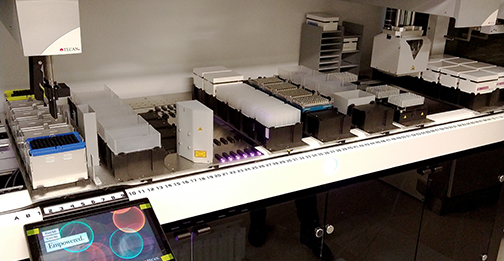

LSU Health New Orleans Precision Medicine Lab Earns CAP Accreditation

The Precision Medicine Laboratory at LSU Health New Orleans School of Medicine has been fully accredited by the College of American Pathologists. More

LSU Health New Orleans Awarded $2.38M to Sequence COVID-19 Virus Variants

LSU Health New Orleans has been awarded $2.38 million in funding to lead partnerships to sequence SARS-CoV-2 variants. The funding is from a contract with the Louisiana Department of Health (LDH)) and a National Institute of General Medical Sciences supplement to the LACaTS (Louisiana Clinical & Translational Science Center) grant. More